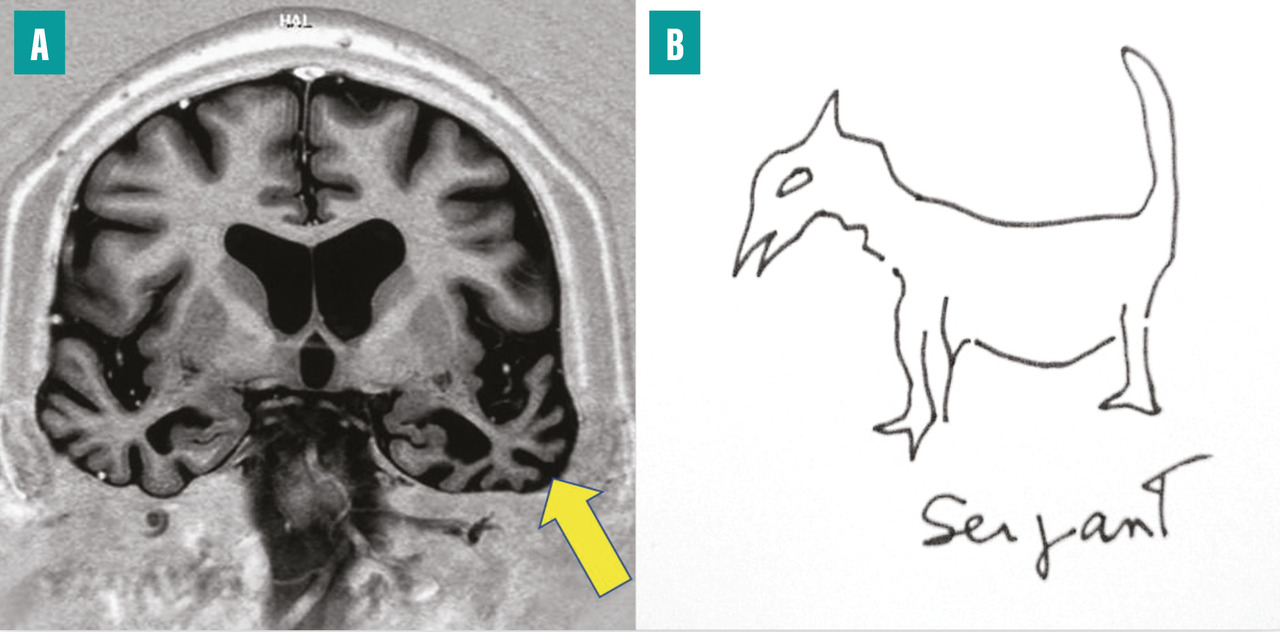

Décrit initialement en 1881 chez des alcooliques, en association avec une polyneuropathie, l’origine du syndrome de Korsakoff est éthylo-carentielle. Depuis lors, d’autres causes carentielles ont été identifiées, parmi lesquelles l’hyperémèse gravidique (vomissements incoercibles du premier trimestre de la grossesse) ou les complications de la chirurgie bariatrique. Leur point commun est la carence en vitamine B1, à l’origine d’une nécrose hémorragique des corps mamillaires (fig. 4) et/ou des lésions des noyaux antérieurs et dorso-médians du thalamus,4 qui interrompent de façon bilatérale le circuit de Papez (voir l’article « Anatomie de la mémoire » page 1072 ).

Ce tableau est dû à une maladie neurodégénérative qui touche le néocortex temporal, singulièrement le cortex périrhinal et le pôle temporal antérieur, de façon asymétrique (fig. 5A ). Le pôle temporal joue le rôle de nœud de connexion pour accéder à la mémoire sémantique, c’est-à-dire à toutes les connaissances générales distribuées dans le cerveau. Le tableau est singulier : le malade garde une bonne mémoire au jour le jour et sa mémoire autobiographique, mais il perd des pans entiers de son savoir (sur les animaux, les outils, la géographie, etc.). Le langage est fluide, mais il existe un manque du mot, masqué par des circonlocutions ou des mots valises (truc, machin), des mots génériques. Les mots ne sont non seulement pas trouvés, mais ils ne sont plus non plus associés à leur sens (fig. 5B ). L’écriture se fait avec des erreurs phonologiquement correctes (« agraphie de surface »). Les patients restent assez autonomes de nombreuses années, dans leur environnement habituel. C’est une des raisons pour lesquelles on tend à renoncer au terme de démence sémantique au profit de celui d’« aphasie progressive, variant sémantique », bien que la clé des déficits soit un trouble de la mémoire. Ce tableau est une des formes cliniques des dégénérescences lobaires fronto-temporales (DLFT). Sur le plan neuropathologique, on observe le plus souvent des inclusions neuronales dites TDP-43 de type C.9